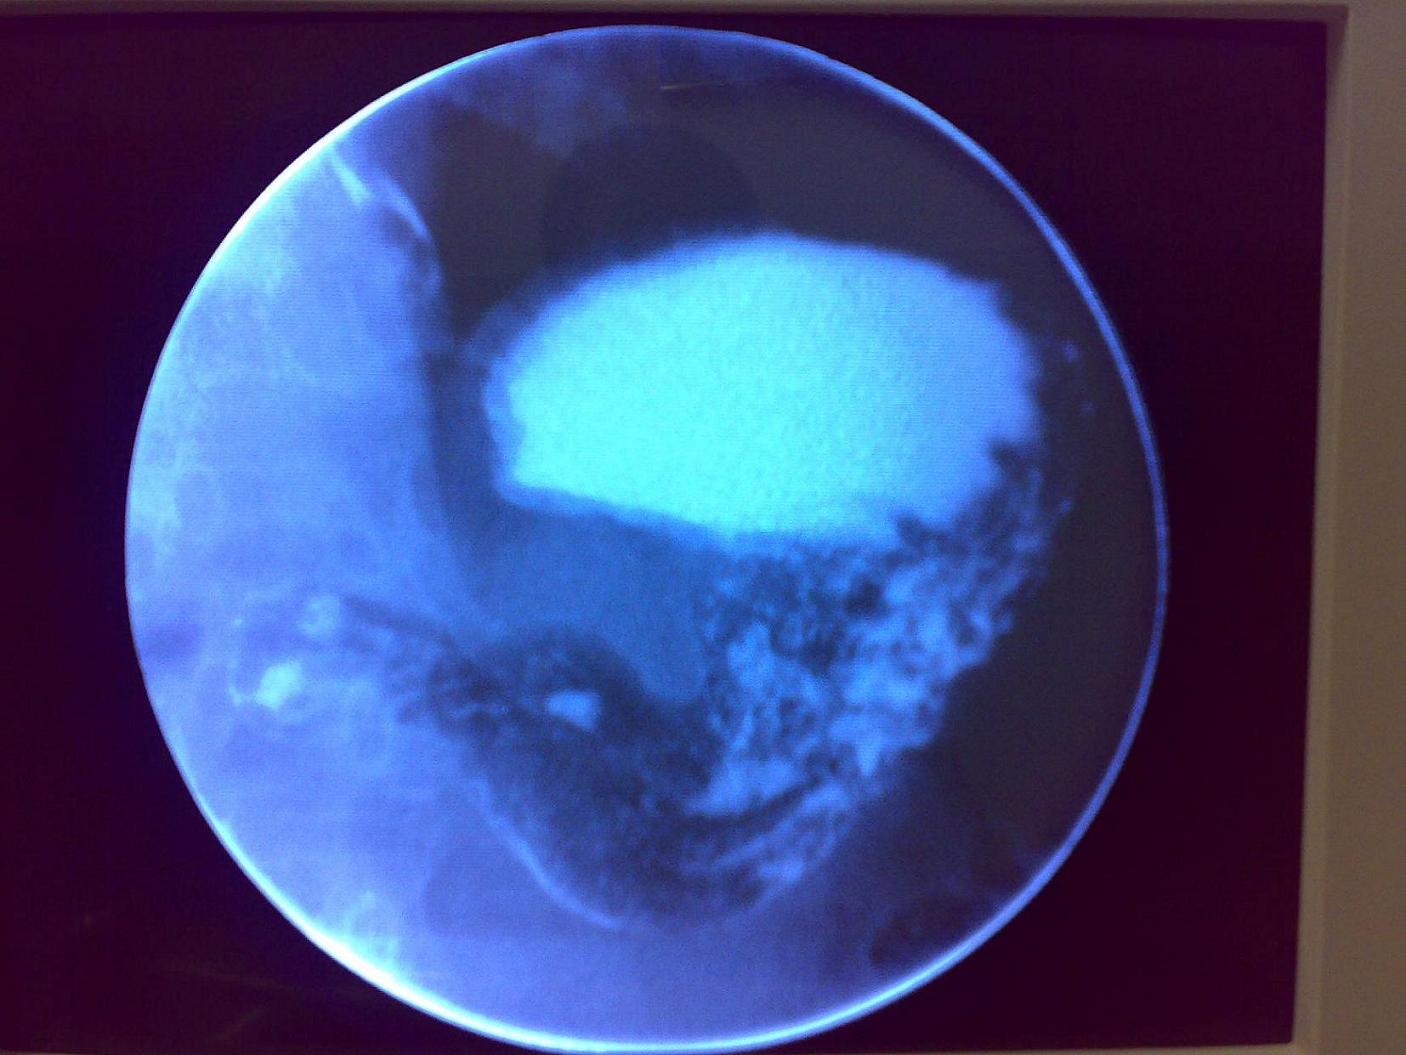

标题: X4144:女 52y 胃痛多年。。。

听说是本院一职工的亲戚,没有开单,我是在透视机上无意中看到,手机所拍下的。病史不详,请谅解。

胃溃疡,龛影,胃粘膜聚集,典型。

见胃体局限性粘膜呈脑回状增厚且不规则,胃窦部腔内见扁圆型龛影,在近地壁呈“满穴”现象.

考虑∶〔局限型〕胃粘膜巨大肥厚症或胃恶性淋巴瘤可能,胃窦部溃疡,建议胃镜活检.

龛影,胃粘膜聚集,典型胃溃疡。

从现在图象看应该是龛影,不过可惜没有显示出龛影切线位,这样看的话黏膜显示也不是很理想,不过根据龛影大小来判断我首先考虑单纯胃溃疡.